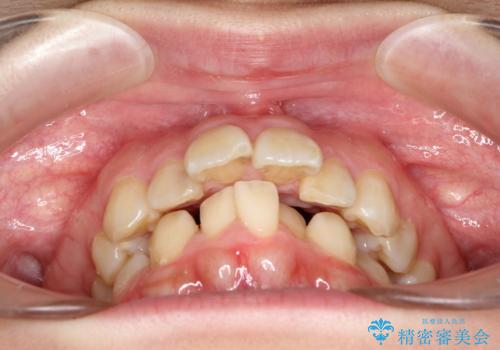

- 口元の閉じにくさと、前歯のでこぼこの歯並びを気にして来院された患者様です。

口元を積極的に引っ込めるために、上下左右の小臼歯計4本を抜歯することとしました。

咬み合わせが深く、咬合力強いため、補助装置を使用しながら積極的に口元を下げることとしました。